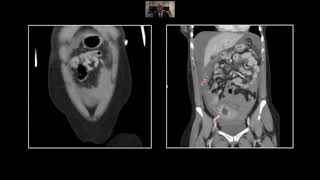

Pancreatic Emergencies | Interesting Radiology Cases

Pancreatic Emergencies | Interesting Radiology Cases Interactive CT Abdo Cases - Pancreatitis and Complications (Intro Level)

Imaging in Pancreatitis Acute Pancreatitis and Complications on CT

Acute Pancreatitis and Complications on CT